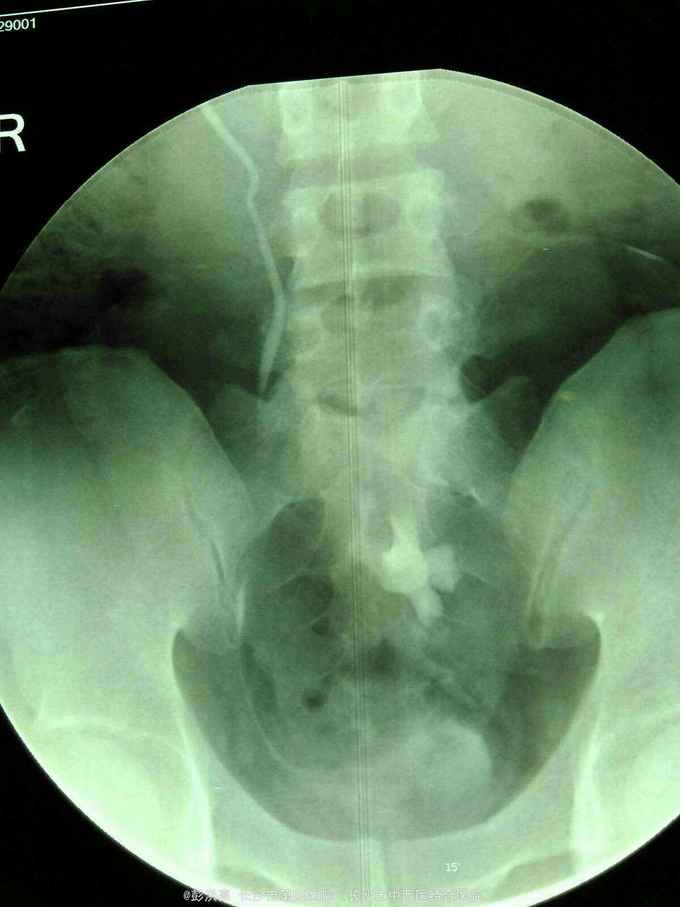

男性,25岁,左腰痛入院。2年前在外院发现左侧盆腔异位肾并肾盂输尿管移行处结石行腹腔镜下切开取石术。现CT示左侧盆腔异位肾并多发结石。术前其他检查正常。

请问该患者如何处理。